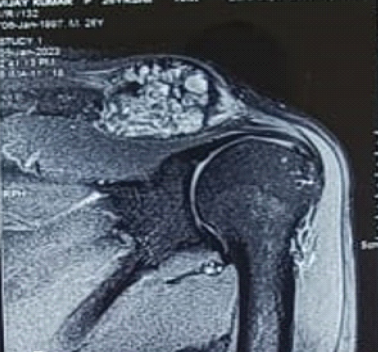

Post-operative Microdiscectomy Complicated by Lumbar Epidural Hematoma with Cauda equina Syndrome Following Dual Viral Infection: A Rare Case Report and Its Management